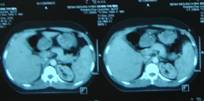

CT ổ bụng: gan-lách to, không có hạch ổ bụng, không có dịch ổ bụng

Kết quả chụp CT ổ bụng: gan, lách trong giới hạn bình thường